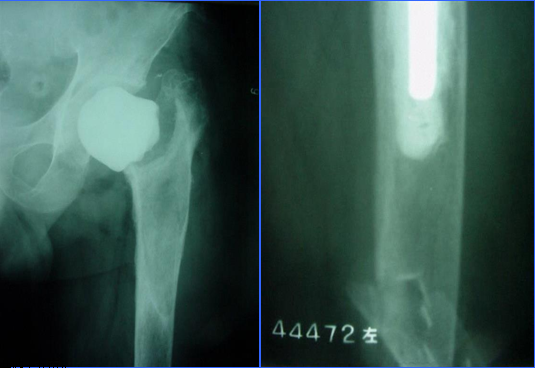

髓内固定:(一)髓内针

·逆行髓内针可用来处理发生在假体尖端以远的骨折 ;

·早期有人使用弹性髓内针处理发生在人工股骨头置换术后假体远端的骨折,如Rush氏钉和Ender氏钉 ;

·带锁髓内针:在假体和髓内针之间不要留有空隙,否则术后此部位应力增加,易造成新的骨折;

髓内固定:(二)翻修术

①适应征:假体松动的骨折

②原则:

尽可能的保留骨量

尽可能使假体与完整的宿主骨之间获得牢固固定

③假体的选择

长柄远端固定非骨水泥型

假体的长度至少要超过骨折端两倍于股骨直径的距离

骨缺损者,联合异体皮质骨板髓外固定